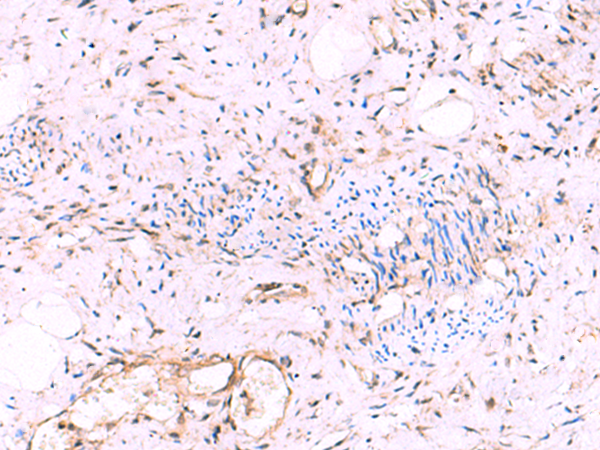

分类: 科研抗体货号: P10202别名: GST2; ERF3B应用: WB,IHC反应种属: Human, Mouse